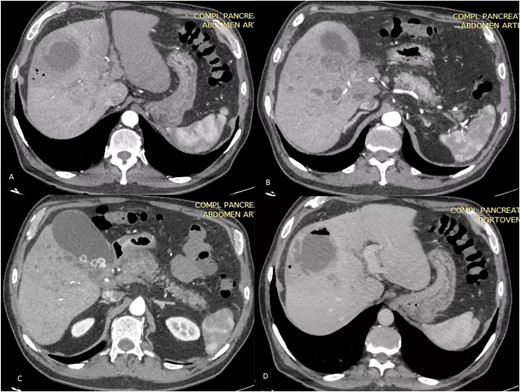

However, 1 month later, the patient had persistent fever and abdominal pain in the epigastric region. He also complained of anorexia, chills, and liquid stools with and temperature on 39°C. The laboratory test reveals a white blood cell count of 26.7× 103/μl, indicating a left shift in neutrophils at 88.3%. The blood biochemistry analysis revealed the following results: total bilirubin, 2.53 mg/dL (normal range 0.30-1.00); direct bilirubin, 1.21 mg/dL (normal range 0.03-0.18); indirect bilirubin, 1.32 mg/dL (normal range 0.27-0.82); albumin, 2.82 (normal range 3.70-5.30); alanine aminotransferase (ALT), 130 IU/L (normal range 7-52); aspartate aminotransferase (AST), 128 IU/L (normal range 13-39); gamma glutamyl transferase (GGT), 263 IU/L (normal range 9-64); alkaline phosphatase, 528 IU/L (normal range 34-104); lactic dehydrogenase (LDH), 214 IU/L (normal range 140-221); amylase, 38 IU/L (normal range 29-103); lipase, 13 IU/L (normal range 11-82); C-reactive protein (CRP), 25.3 mg/dL (normal range 01.000-03.000). We performed a contrasted computer tomography reviewed hepatic abscess (Fig. 3A and B) in segment VIII and V with a volume of 100 mL associated with smaller pericholangiolar abscesses of diffuse distribution, also reported a complete thrombosis of the right branch of the portal vein with partial extension to the main portal vein (Fig. 3D) and free fluid in the pelvic cavity.

Axial TC on shows liver of regular contours, heterogeneous at the expense of multiple collections that follow the course of the bile duct of diffuse distribution. A and B on different sections: abscess on segments V and VIII, measures 58 × 56 × 67 mm in its major axes and has an approximate volume of 100 cc, presents air-fluid level. The bile duct measures 3.5 mm. C: Distended thin-walled gallbladder with stones inside with an axis >100 mm and calculous cholecystitis. D: (Venous phase). The portal vein is observed with hypodense material inside with partial defect in filling of the contrast agent at the level of the hilum with complete extension toward the right branch.